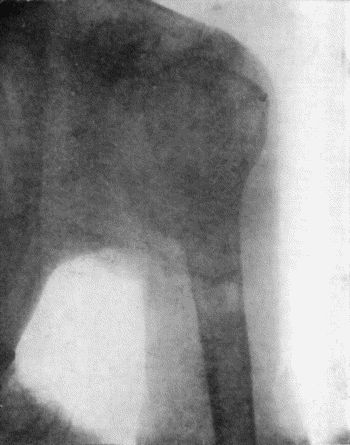

| 121. | Radiogram of Brodie's Abscess in Lower End of Tibia | 451 |